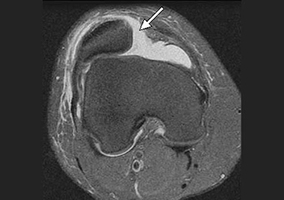

Диагностика. Разрыв передней крестообразной связки подтверждается результатами магнитно-резонансной томографии (МРТ) коленного сустава. Рентгенография не является информативным методом исследования при разрыве ПКС, поскольку мягкие ткани, связки и хрящевые структуры не видны на рентгеновских снимках. На МРТ возможно выявить не только признаки повреждения ПКС, но и сопутствующие травмы менисков и хрящевого покрова сустава.

Артроскопическая картина проведения трансплантата ПКС